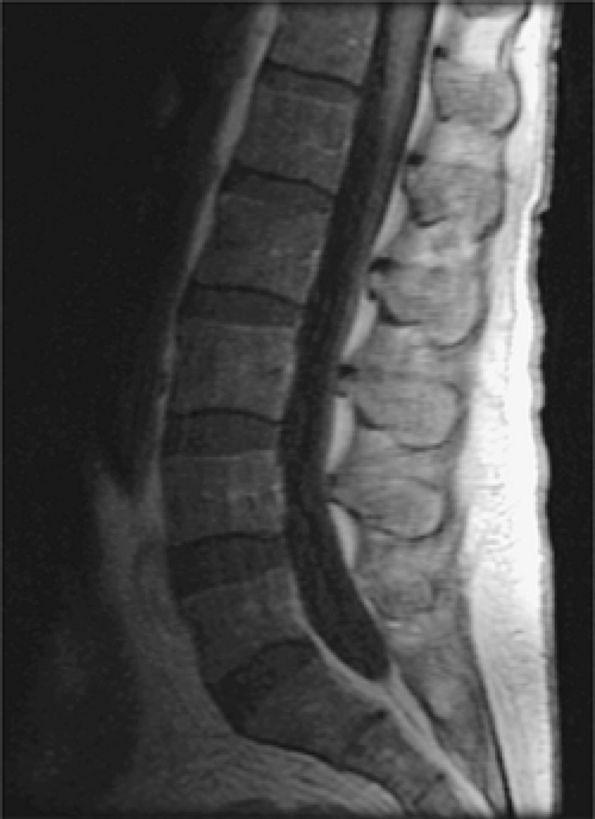

FIGURE 13.11 ● Diffuse low-signal-intensity leukemic infiltration of marrow occurs in acute lymphocytic leukemia, as seen on T1-weighted sagittal images of the cervical (A) and thoracolumbar (B) spine.

FIGURE 13.35 ● Diffuse lymphomatous involvement of the spine. Infiltration of the marrow is hypointense on a sagittal T1-weighted image of the lumbar spine simulating leukemic involvement.

![]() |

FIGURE 13.37 ● Fatty marrow infiltration following radiation therapy for non-Hodgkin lymphoma. Sagittal T1-weighted image of the cervical spine shows diffuse bright-signal vertebral bodies (arrows).